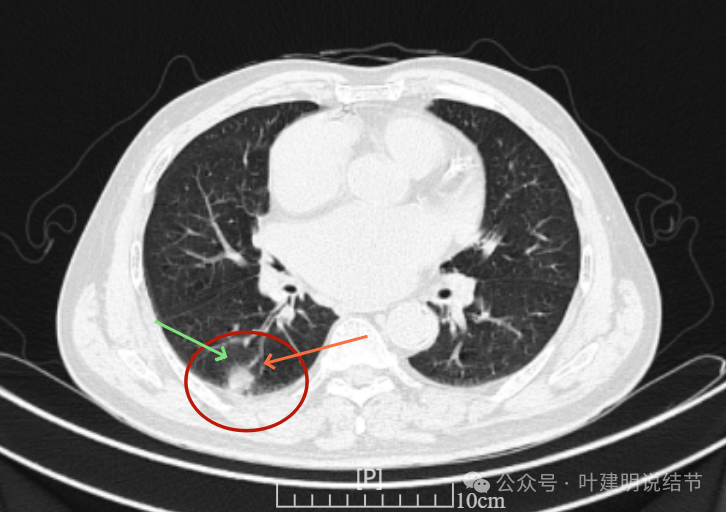

我们先来看2022年3月主要病灶的影像:

右上叶结节实性,密度高,边缘平整,轮廓清楚,像良性些。

右下似见微小结节,实性,与边上小血管截面不太好区分,过小没什么临床意义,能随访。

左下胸膜下实性结节,轮廓稍模糊,密度较高,边缘较光,像淋巴结些,能随访。